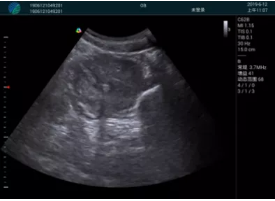

甲狀腺囊性結(jié)節(jié),囊壁鈣化,透聲好

甲狀腺囊性占位